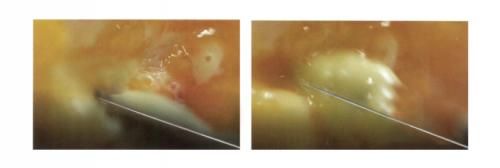

維密金雕·Plasma精準汽化脂肪FAT

采用組織汽化的工作方式,以超低頻率100KHz電能激發(fā)介質(zhì)(Nacl)產(chǎn)生等離子體,等離子體中的高速帶電粒子直接打斷分子鍵,使靶組織裂解成低分子量氣體,因為頻率低,在40~60℃的低溫環(huán)境下使脂肪組織

細胞解體從而實現(xiàn)微創(chuàng)效應(yīng)。